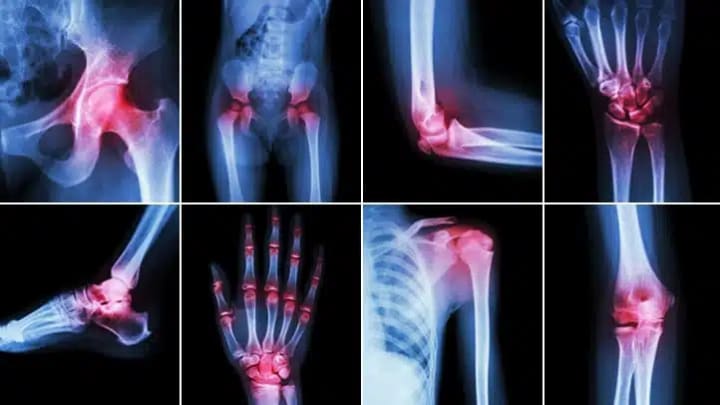

The word "arthritis" refers to inflammation of the joints. It is not a single disease but rather a group of over 100 related conditions that affect joints, surrounding tissues, and other connective structures. While arthritis can impact individuals of any age, it is more common among older adults. The condition can cause significant discomfort and interfere with daily activities due to chronic pain and restricted movement.

There are various forms of arthritis, each with distinct characteristics and causes. The most prevalent types include:

1. Osteoarthritis (OA)

• The most widespread form of arthritis.

• Develops due to the gradual degeneration of joint cartilage.

• Commonly affects the knees, hips, hands, and spine, leading to pain and stiffness.

2. Rheumatoid Arthritis (RA)

• An autoimmune disorder where the immune system mistakenly attacks the joints.

• Leads to chronic inflammation, pain, and potential joint deformity.

• Often impacts joints symmetrically on both sides of the body.